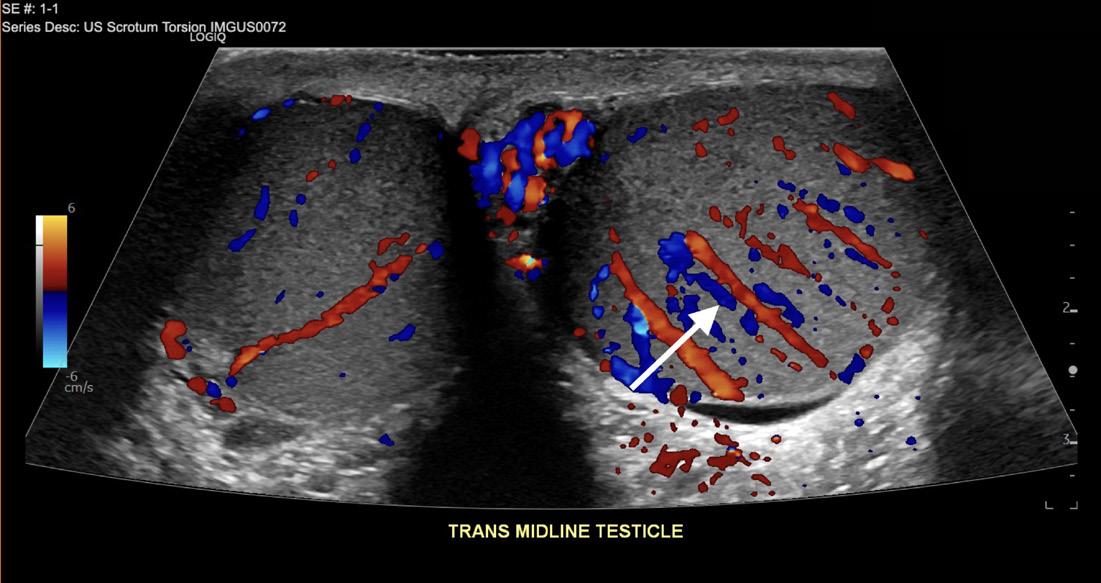

327 19-Year-Old with Sudden Onset Left Testicular Pain E Small, N Ashenburg, K Schertzer

1 4%